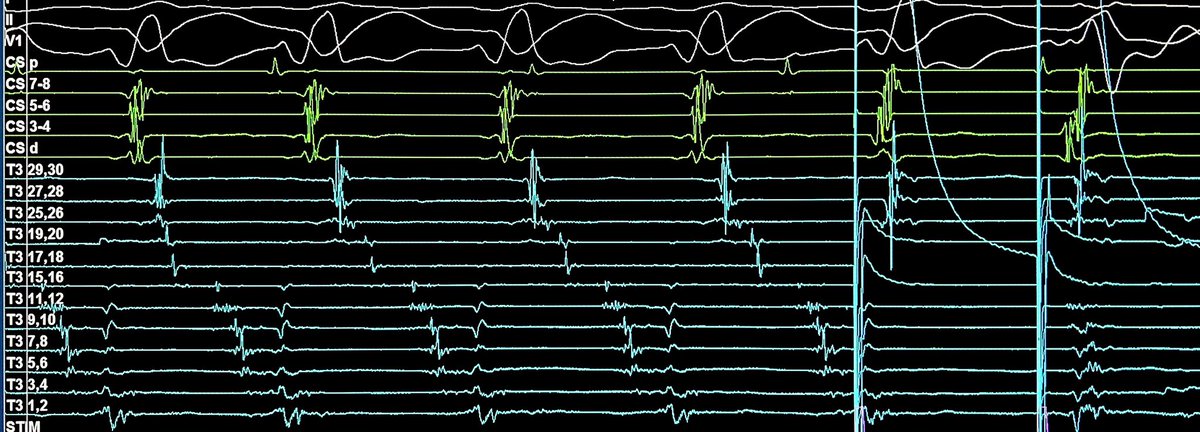

A beautiful EGM from our new High Density Linear mapping catheter - the T3-VT: 1-1-1 spacing/6F. It is wonderful to see such clarity in an EGM. Thanks to all who helped in its design. Please contact me for further details @DrRoderickTung #Ablatevt @APTEPInc #EPeeps #HDmapping